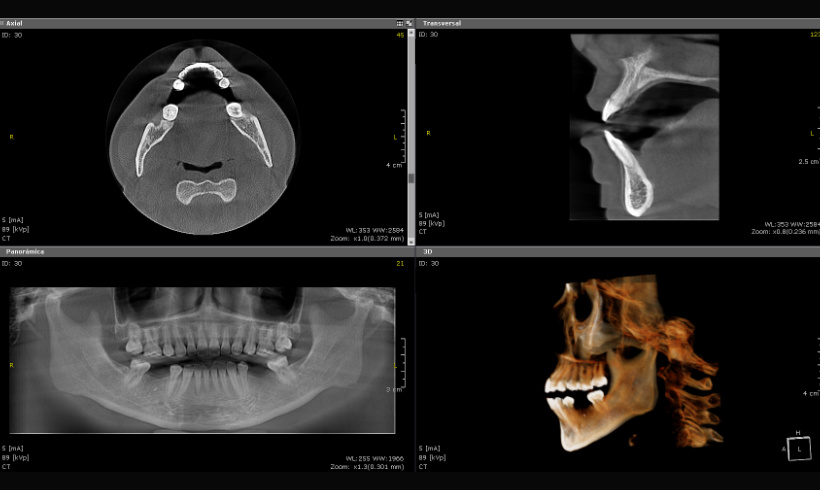

La tomografía, junto con el escaneo nos permite realizar guías quirúrgicas para la colocación de implantes, alargamiento de coronas, colocación de mini implantes de ortodoncia, tratar endodóndicamente dientes calcificados.

Tomografía para guías quirúrgicas